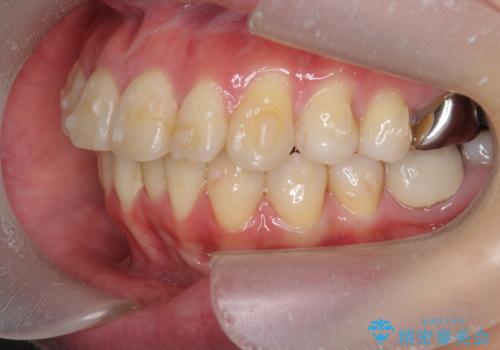

捻れた奥歯 突き出た前歯を治したい

- 出っ歯に見える前歯、捻れてしまった小臼歯の改善を求めて来院されました。

マウスピースでは改善の難しい小臼歯のねじれをまず部分ワイヤー矯正で改善し、その後マウスピース矯正で前歯の突出感を改善します。

時間はかかりましたが、捻れ、かみ合わせ、前歯の角度の改善が達成され満足いただくことができました。